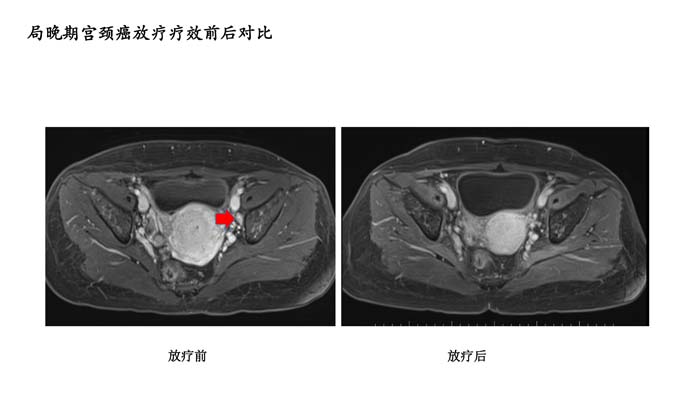

上一篇: 局晚期宫颈癌放疗疗效前后对比5